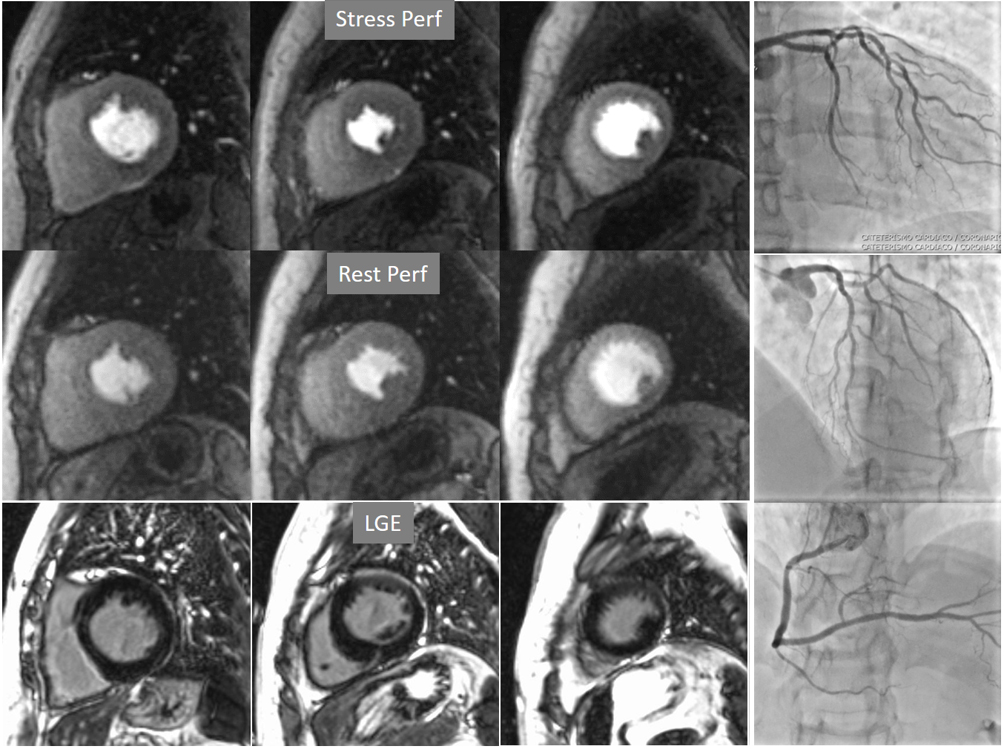

Perfusion defects in different territories can be detected in case of multivessel disease (Fig. 7) and, in patients with severe 3-vessel CAD, the perfusion study may show a global, intense, persistent defect which is readily recognizable (Fig. 8).

Fig. 7.Two-vessel perfusion defect. Stress perfusion defects at the anterior (white arrows) and inferior (black arrows) walls, not present at rest. Angiography (right panels) shows significant stenoses (white arrows) of the LAD (upper panel) and the right coronary artery (RCA) (lower panel).